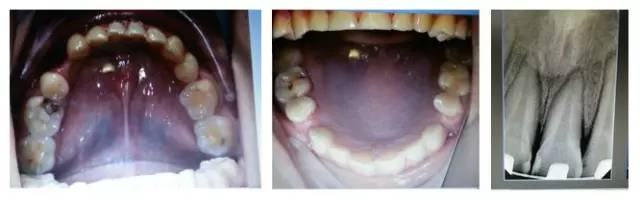

(以下為治療后的照片:患者癥狀得到了良好改善。)

6.jpg

足以看出,尖牙保護(hù)(牙合)在臨床工作中的重要作用,它是以尖牙為支撐,對(duì)其他牙齒起到保護(hù)作用。其特點(diǎn)是正中關(guān)系(牙合)與正中(牙合)協(xié)調(diào);側(cè)方咬合運(yùn)動(dòng)時(shí),工作側(cè)只有尖牙保持接觸非工作側(cè)牙齒不接觸;在作前伸咬合運(yùn)動(dòng)時(shí),上下頜前牙切緣相對(duì)接觸,后牙不接觸。尖牙具有適合制導(dǎo)的舌面形態(tài),可使用(牙合)力趨于軸向;牙根長(zhǎng)且粗大,支持力強(qiáng);尖牙位居牙弓前部,在咀嚼時(shí)構(gòu)成第Ⅲ類(lèi)杠桿,能抵御較大的咀嚼力;以及尖牙牙周膜感受器豐富,對(duì)刺激敏感,能及時(shí)調(diào)整反應(yīng)都是尖牙的有利條件。尖牙形態(tài)的恢復(fù)在此例正畸治療中,對(duì)前牙、后牙都起到了很好的保護(hù)作用,也能保證后期按照標(biāo)準(zhǔn)(牙合)進(jìn)行(牙合)重建時(shí)后牙無(wú)干擾。功能在先,美觀在后,權(quán)老師為您展示了這樣的治療理念。